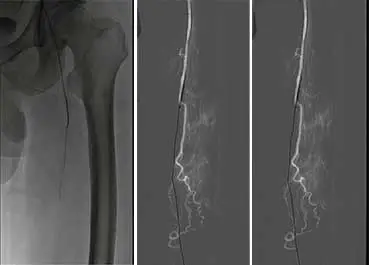

1、仰臥位,常規消毒鋪巾,2%利多卡因局麻。右股動脈穿刺入路,穿刺置管后,造影示:主動脈下段血流尚通暢,雙側髂總動脈輕度狹窄,髂外動脈及股總動脈血流通暢,右側股淺動脈、腘動脈輕度狹窄,左股淺動脈全程狹窄大于50%,中遠段閉塞約12cm。左腘動脈及雙側膝下流出道血流通暢。

4、減容后,以SABER3mm*30cm球囊預擴張。

5、使用Matrix Super PTX (巴泰醫療)5mm*20cm及5mm*15cm約束型藥物涂層球囊全程擴張左股淺動脈病變。